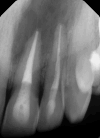

This case report highlights the successful healing of a large periapical lesion through non-surgical root canal retreatment. A 29-year-old male patient presented with a significant radiolucency associated with teeth #21 and #22, initially treated non-surgically. Despite the lesion's size, the treatment, which included thorough canal disinfection and obturation, led to substantial healing. A follow-up cone-beam computed tomography (CBCT) scan after one year confirmed the buccal cortical bone reformation and improvement in the incisive canal area except for the apical region of #21. Subsequently, root canal retreatment was performed for #21. Complete healing was achieved after two years, demonstrating that even extensive periapical lesions can be effectively treated with non-surgical endodontic retreatment, avoiding invasive surgical intervention.